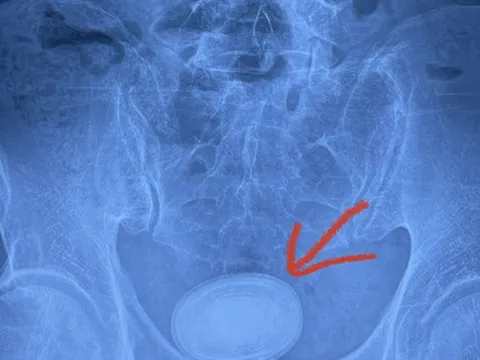

Người đàn ông có viên sỏi kích thước 6cm trong bàng quang

Trung tâm Y tế huyện Yên Lập (Phú Thọ) vừa phẫu thuật thành công trường hợp có sỏi bàng quang lớn bằng kỹ thuật tán sỏi ngược dòng.